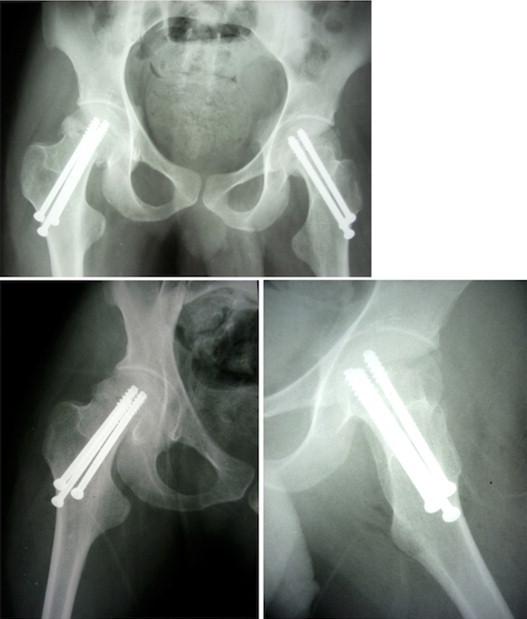

This report presents a case of bilateral femoral neck fractures that occurred during an epileptic attack in a 24-year-old male with mental retardation. His complaints had started after a grand mal epileptic attack 10 days earlier. Bilateral displaced femoral neck fractures (Garden type 4) were seen in lateral radiographs of both hips. The patient was operated on urgently, with closed reduction, three stainless steel cannulated screws, and internal fixation applied to both hips. At postoperative week 12, solid joining was achieved and active walking with complete loading was started.

本报告呈现了一例24岁智力发育迟缓男性在癫痫发作时发生双侧股骨颈骨折的病例。他的症状在10天前一次大发作癫痫后开始出现。双髋部侧位X线片显示双侧股骨颈骨折移位(Garden 4型)。患者接受了紧急手术,进行了闭合复位,在双髋部应用了3枚不锈钢空心螺钉并进行内固定。术后第12周,实现了牢固愈合,并开始完全负重的主动行走。